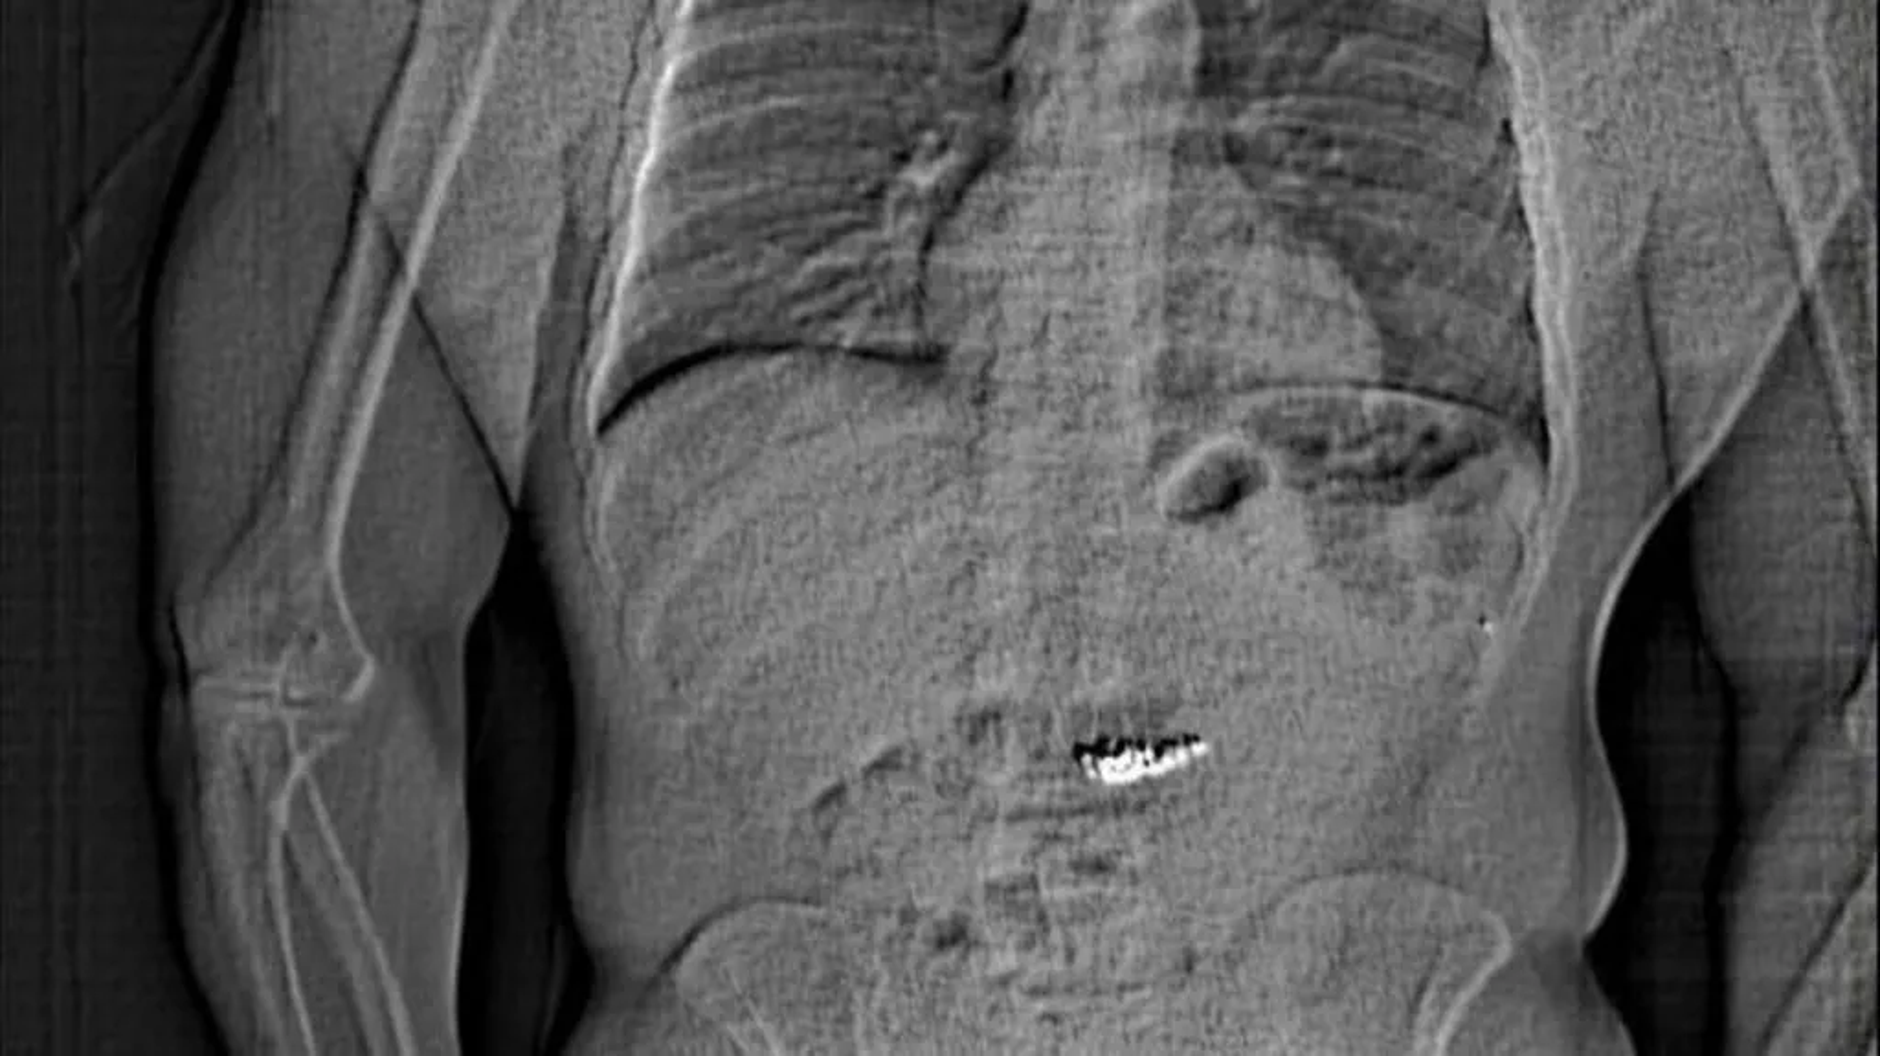

Policija je objavila tudi rentgenski posnetek Gilderjevega želodca, kjer so uhani dobro vidni.